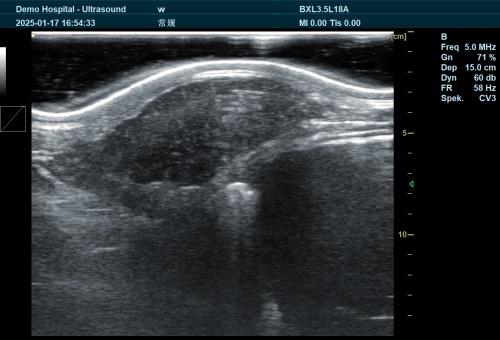

2.1 B‑mode Ultrasound: A Universal Tool

B‑mode scanners generate a grayscale anatomical image. The BXL‑V50, a waterproof handheld model, is favored globally for its durability, species presets, and image clarity. Farmers can switch presets to scan bovine uterine horns one moment and small‑ruminant fetuses the next.

Real-time measurements: crown–rump length, gestational sac diameter, amniotic fluid quantification.